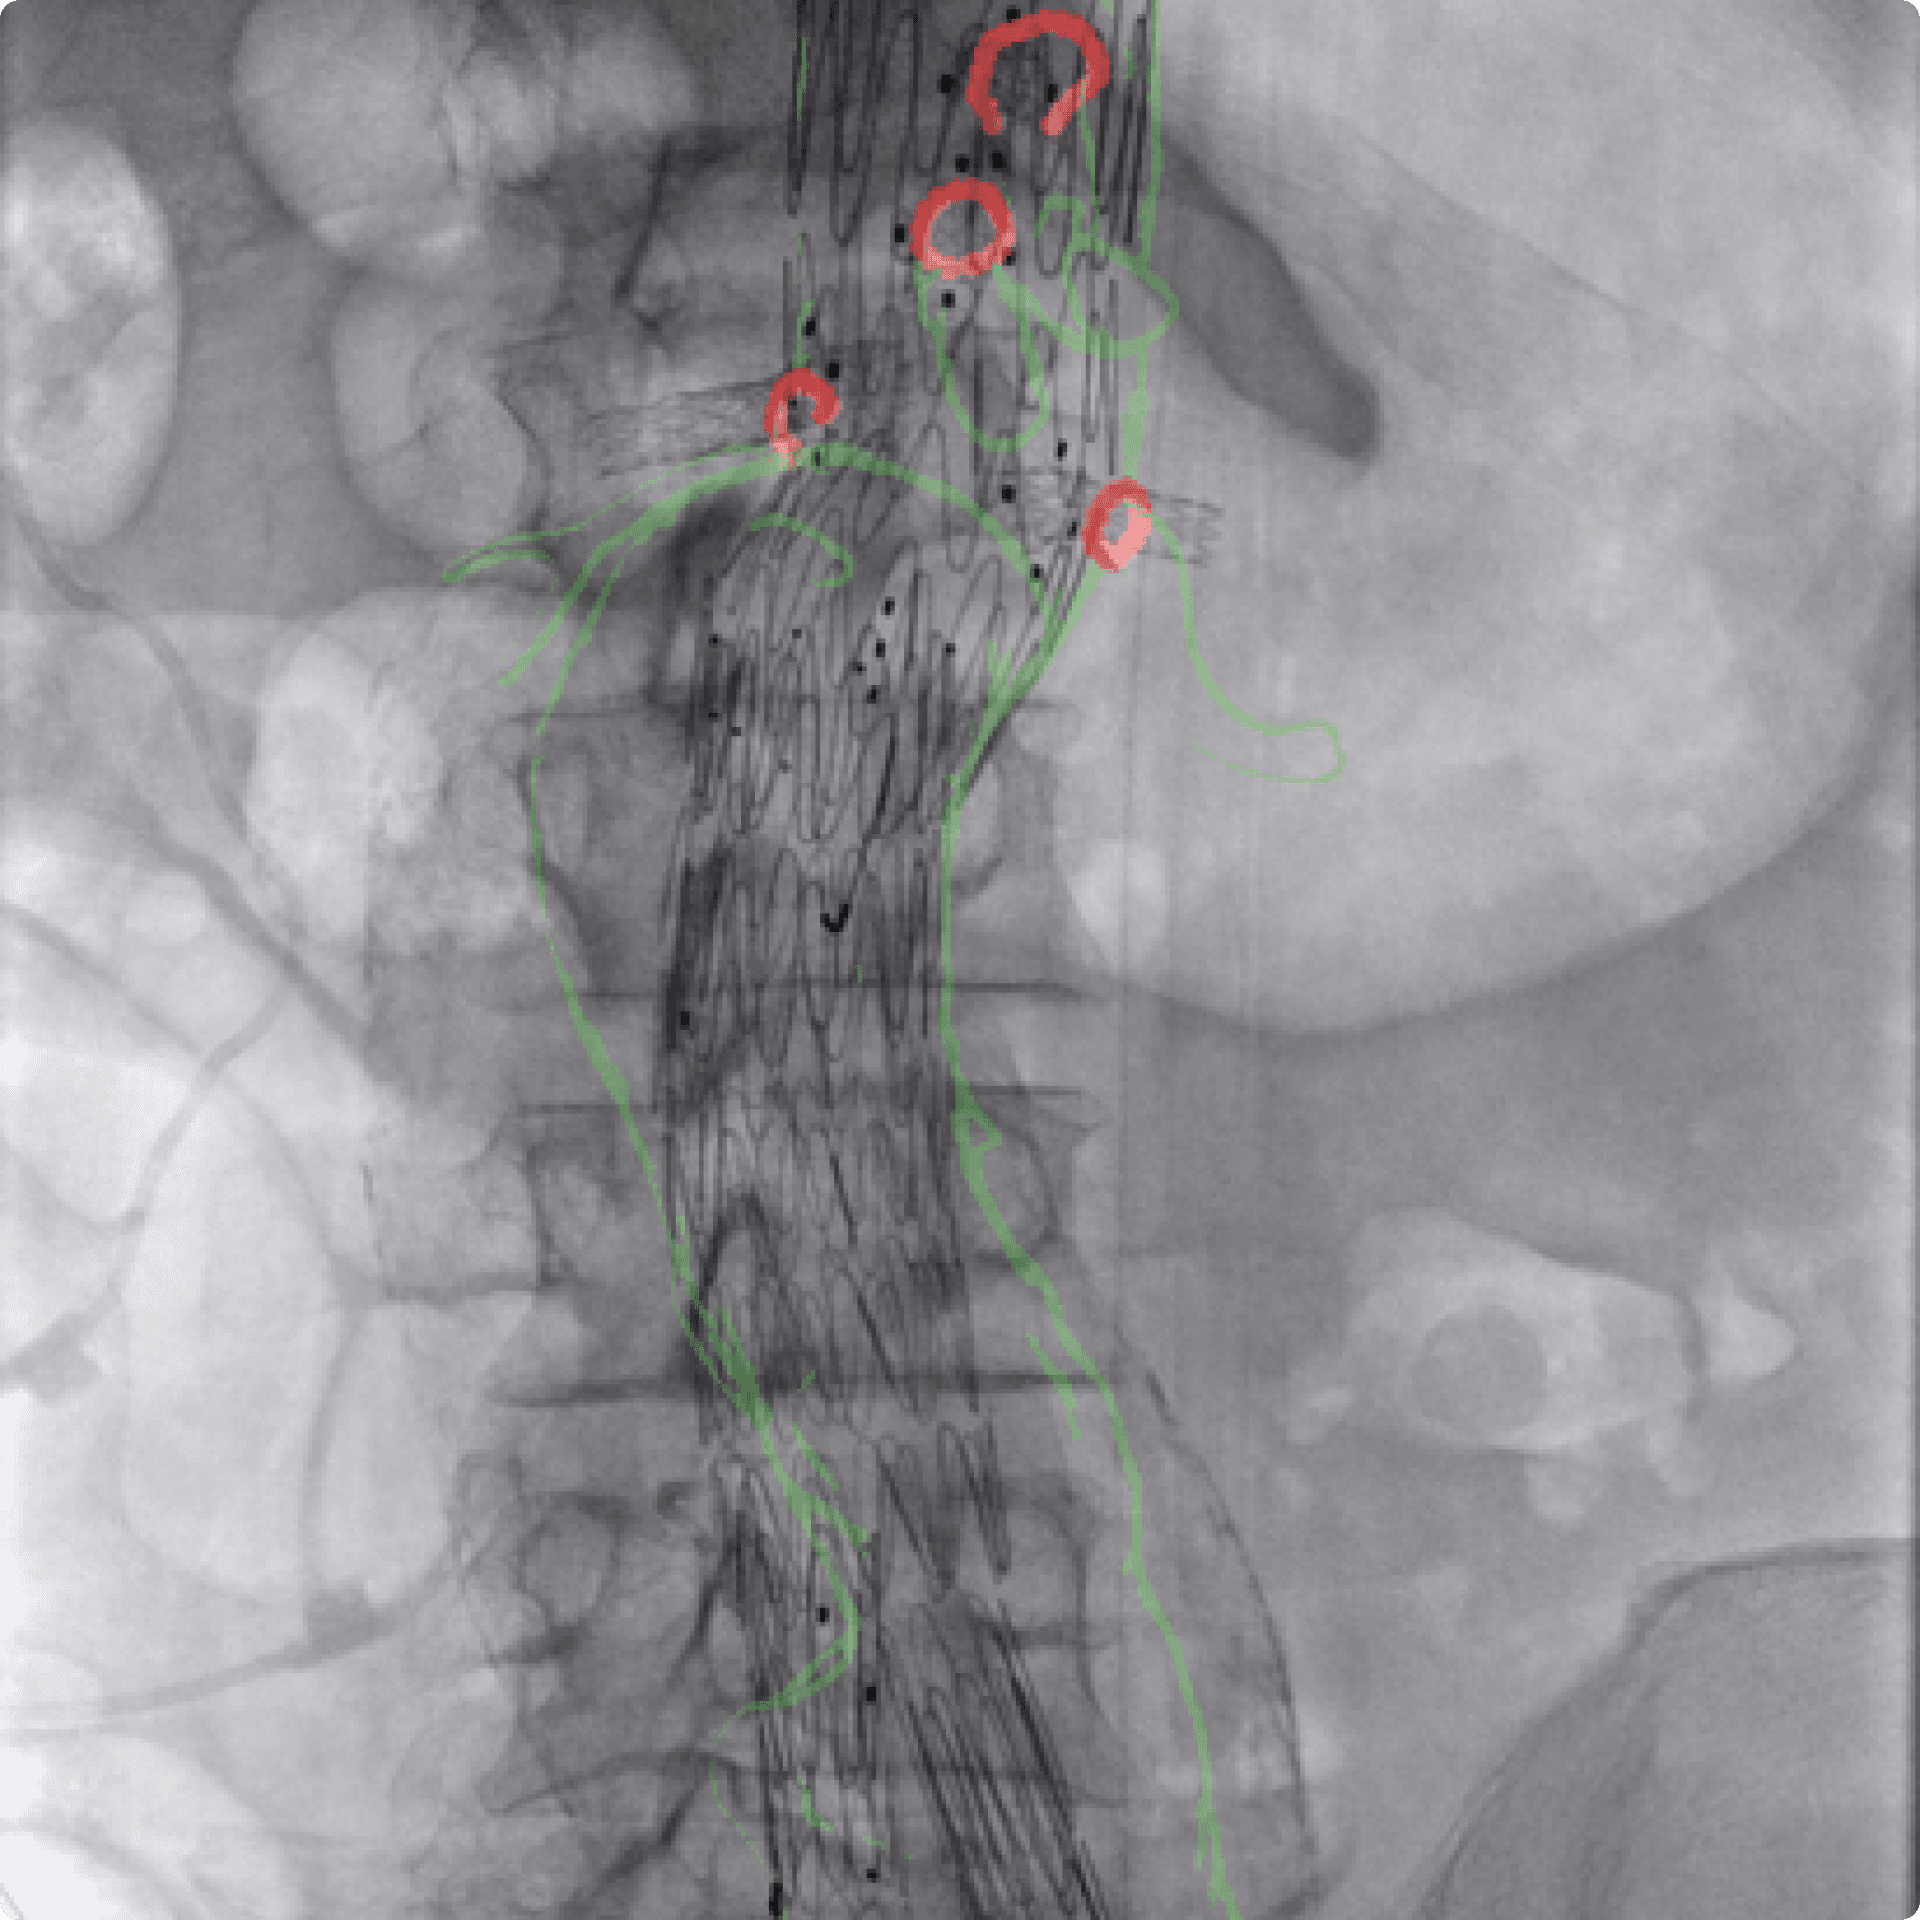

Cydar are a leading provider of cloud-based services that fuse images of patient data with live, x-ray images to provide real-time 3D visualisations of endovascular systems. Using their services reduces radiation risks and patient exposure to chemicals. It also enhances surgical workflow, dramatically improving patient outcomes. After getting feedback from medical professionals who use their system in operating theatres, Cydar acknowledged that they needed to deploy significant usability and user experience improvements. They asked Foolproof to work with them to understand the opportunities.

Through these observation sessions and interviews with surgeons, radiographers, and support staff, we leveraged user-centred principles to design, test and iterate improvements to the interface and visualisation system.

To understand how surgeons interacted with the system during an operation, the most revealing research was conducted during live surgery. The learnings from these sessions provided fundamental, environmental and behavioural insights that had a significant impact on the design. These types of in-depth insights could not have be gained through interviews alone.

Taking the insights from research, we sketched initial concepts for interface components and screens. After testing these concepts with surgeons, we evolved them into high-fidelity screens and a prototype. When testing the prototype, we discovered that the smallest elements of the interface had the biggest impact and provided most value to the surgeons, which forced us to focus on micro-interactions that we may have overlooked otherwise. At its core, the project was all about applying solid experience design methods to extraordinary new environments. Armed with a whole new vocabulary, we relentlessly focused on surgical outcomes. Or, as Tom Carrell co-founder of Cydar put it, "Ultimately, it is all about improving the patient experience".